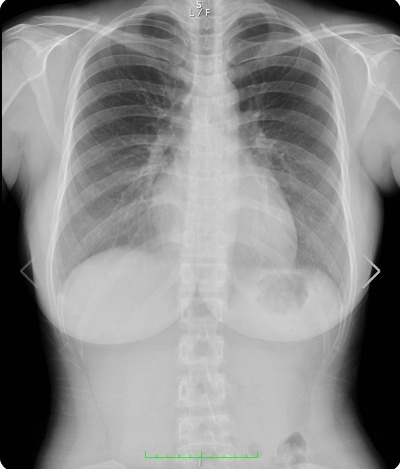

据医美行业专业知识显示,不同隆胸方式在CT影像上的显影效果差异显著。其中,硅胶假体隆胸由于假体本身具有特定密度和规整形状,在CT图像上能呈现出清晰的均匀密度影,边界分明,可轻松被识别;复合式隆胸(假体与自体脂肪结合的方式),因包含硅胶假体成分,同样能通过CT影像检测出来。

但备受关注的是,脂肪隆胸(尤其是浓缩脂肪丰胸,即日本医美领域常见的コンデンスリッチ豊胸),在CT影像上几乎无法显影。据悉,浓缩脂肪丰胸是自体脂肪隆胸的一种,通过特殊技术提取并浓缩自身健康脂肪细胞,再移植到胸部,其脂肪组织与人体正常脂肪组织性质相近,CT难以准确区分,需结合其他检查手段才能综合判断。这也意味着,若模特采用此类隆胸方式,即便公开CT影像,也无法证明其胸部为“天然状态”。